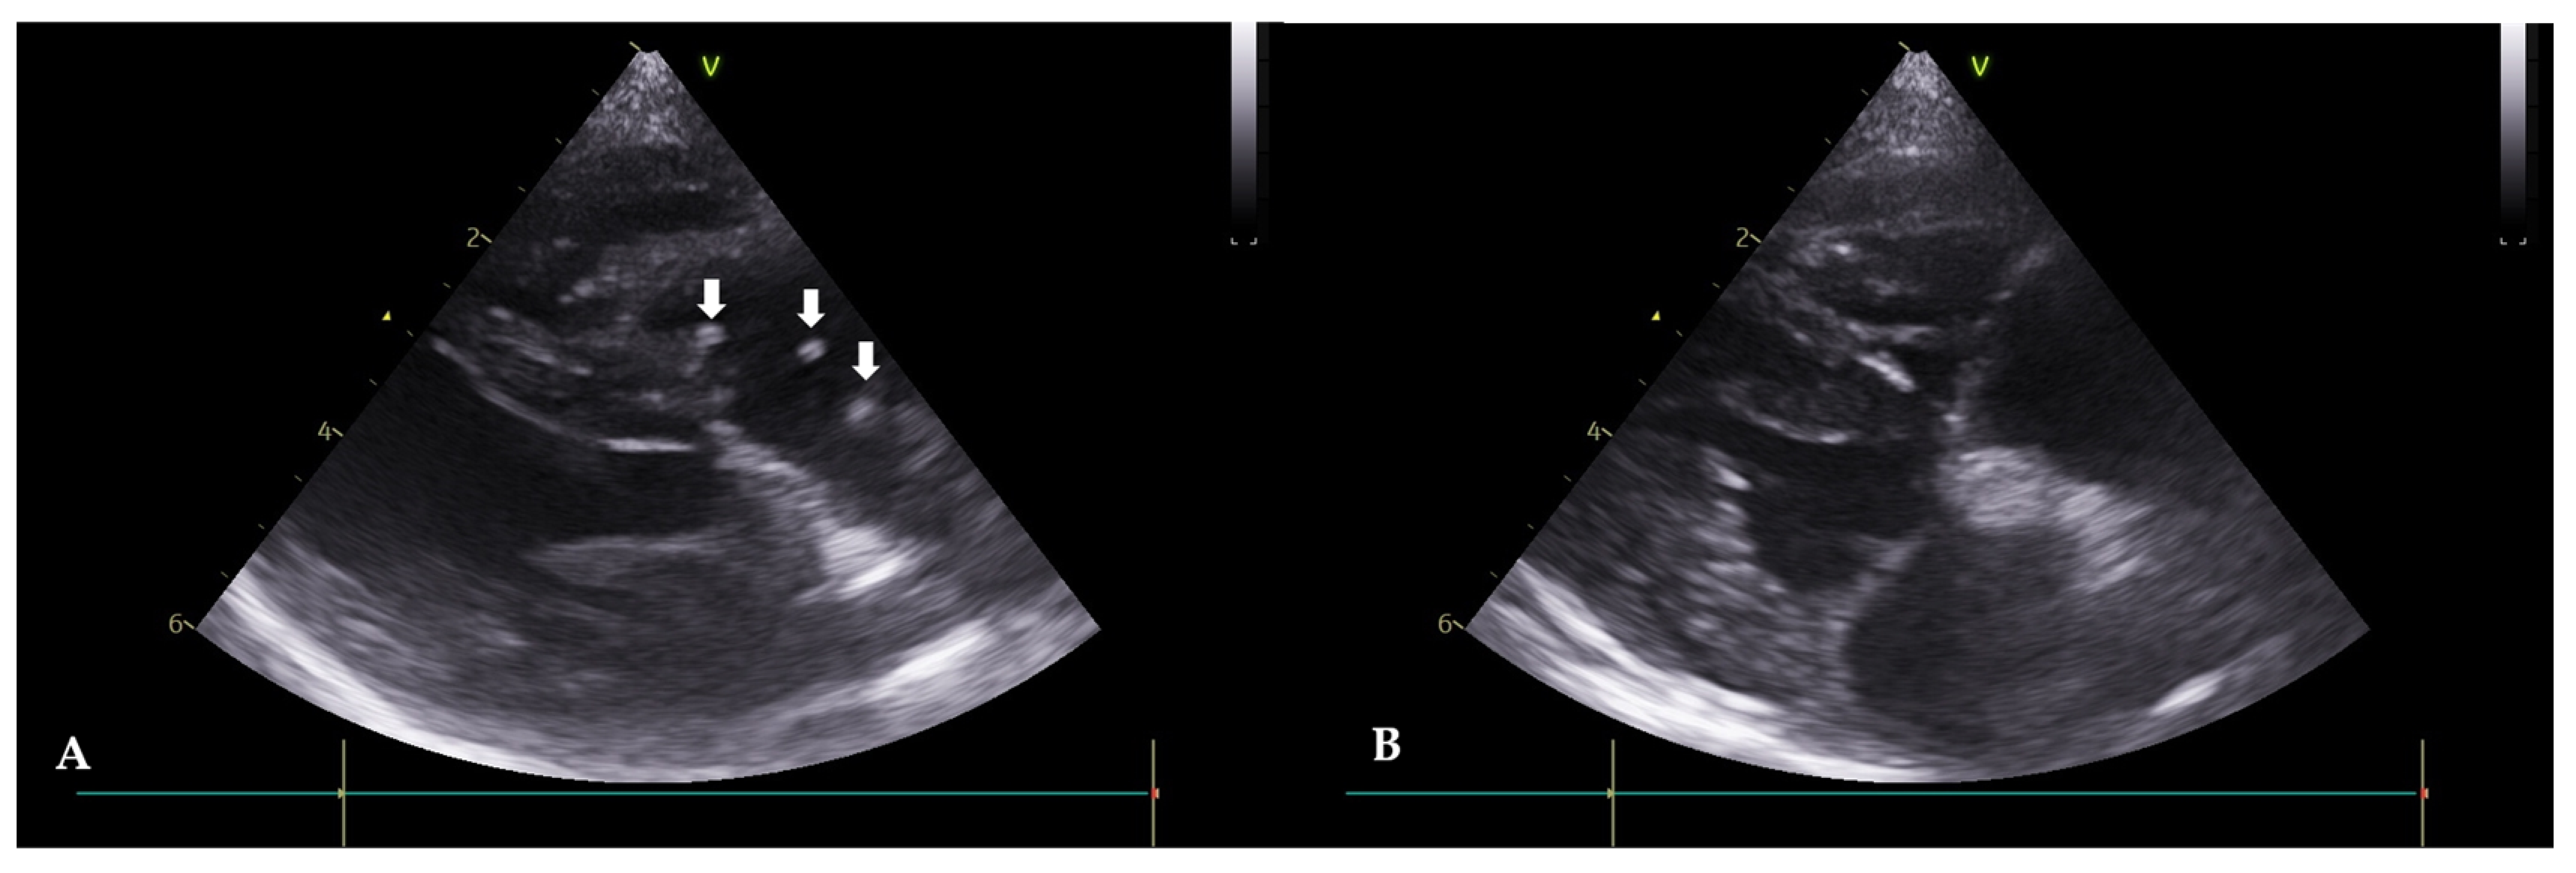

Figure 2. Echocardiograms of Case 1 before (A) and after (B) the heartworm (HW) removal (right parasternal short axis view). (A): Before the procedure, HWs are observed in the right atrium and ventricle (white arrows). (B): After the procedure, HWs are not observed.

A 5-year-old, intact, female mixed-breed dog, weighing 5.2 kg, was referred with symptoms of anorexia and tachypnea. Clinical signs, such as exercise intolerance, mild dehydration, and a pale mucous membrane were observed. An immunological antigen test was positive for adult worms (Rapid CHW Ag 2.0 kit Bionote Co., Gyeonggi, Republic of Korea) and microfilariae were observed in the peripheral blood smear examination. Thoracic radiography revealed a reverse D heart sign, a vertebral heart size (VHS) of 11.5, and enlargement of the pulmonary artery. Echocardiograms revealed double-walled linear echoic structures, indicating adult HWs in the right heart (Figure 2A). Hematology and serum chemistry revealed hemolytic anemia, leukocytosis, and mildly increased hepatic enzyme levels. ALP 365 U/L (alkaline phosphatase, ref. 18–101), ALT 225 (alanine transaminase, ref. 12–101), and AST (aspartate aminotransferase, ref. 17–44). After visiting the clinic, the patient was given medication for three days to reduce potential side effects before undergoing the HW removal procedure. Following the interventional extraction procedure previously described, the patient exhibited an improvement in clinical symptoms. Seven days after the intervention, an improvement in clinical symptoms (vital signs and exercise intolerance) was observed. Adult HWs were not visualized on the echocardiograms (Figure 2B). The case included monitoring for pulmonary hypertension before and after the procedure using PV Vmax, TR Vmax, and TR max PG values. Before the procedure, the PV Vmax was 1.85 m/s, the PV max PG was 13.73 mmHg, the TR Vmax was 3.91 m/s, the TR max PG was 59.77 mmHg, the E peak velocity was 0.67 m/s, and the E/A Ratio was 1.89, and after the procedure, the PV Vmax was 0.81 m/s. The PV max PG was 2.64 mmHg, the TR Vmax was 2.71 m/s, the TR max PG was 29.29 mmHg, the E peak velocity was 0.73 m/s, and the E/A Ratio was 1.58. Pulmonary hypertension improved from a moderate to severe stage to a mild stage, while it was difficult to conclude that there had been an improvement in the left ventricle diastolic function.